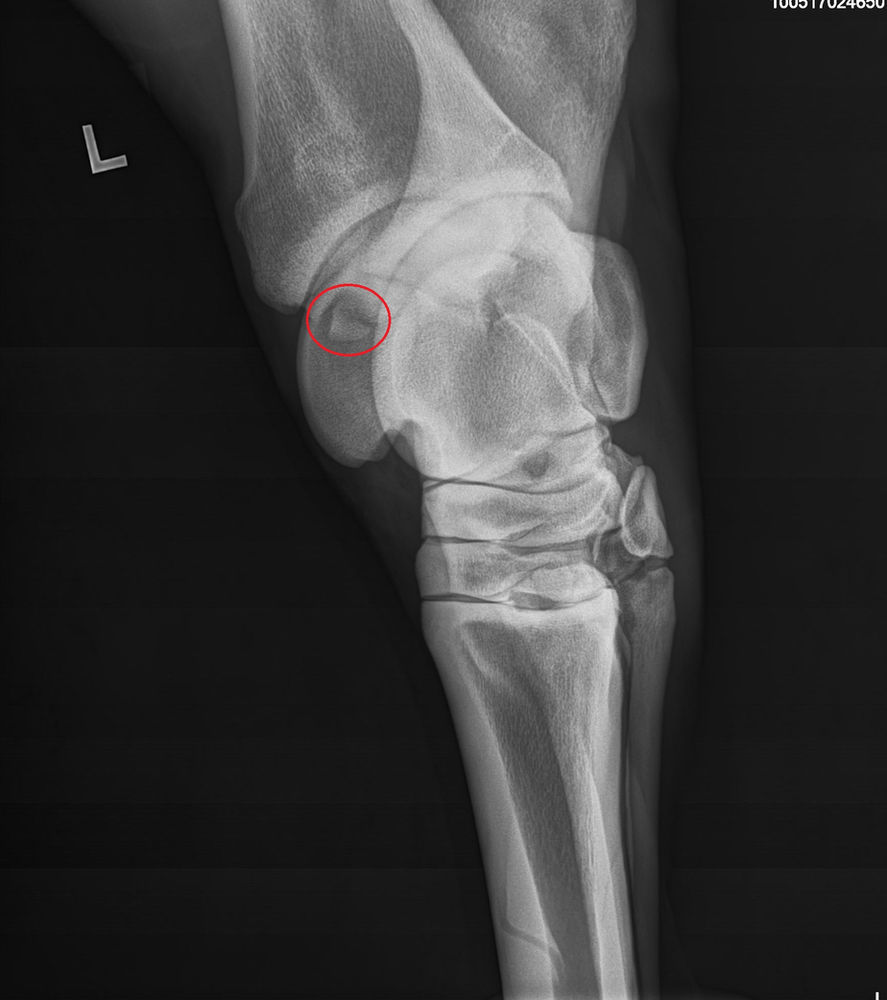

Michael Porter, Equine Veterinarian Cervical Spine Fracture Horse Neck Radiographs diagnostic imaging of the equine neck is undertaken for a wide variety of conditions. taking good neck radiographs in horses requires a thorough knowledge of imaging techniques and cervical spine anatomy. In many cases, radiography is. this chapter discusses the indications for radiography of the cervical spine of the horse, radiographic technique. due to their wide. Horse Neck Radiographs.